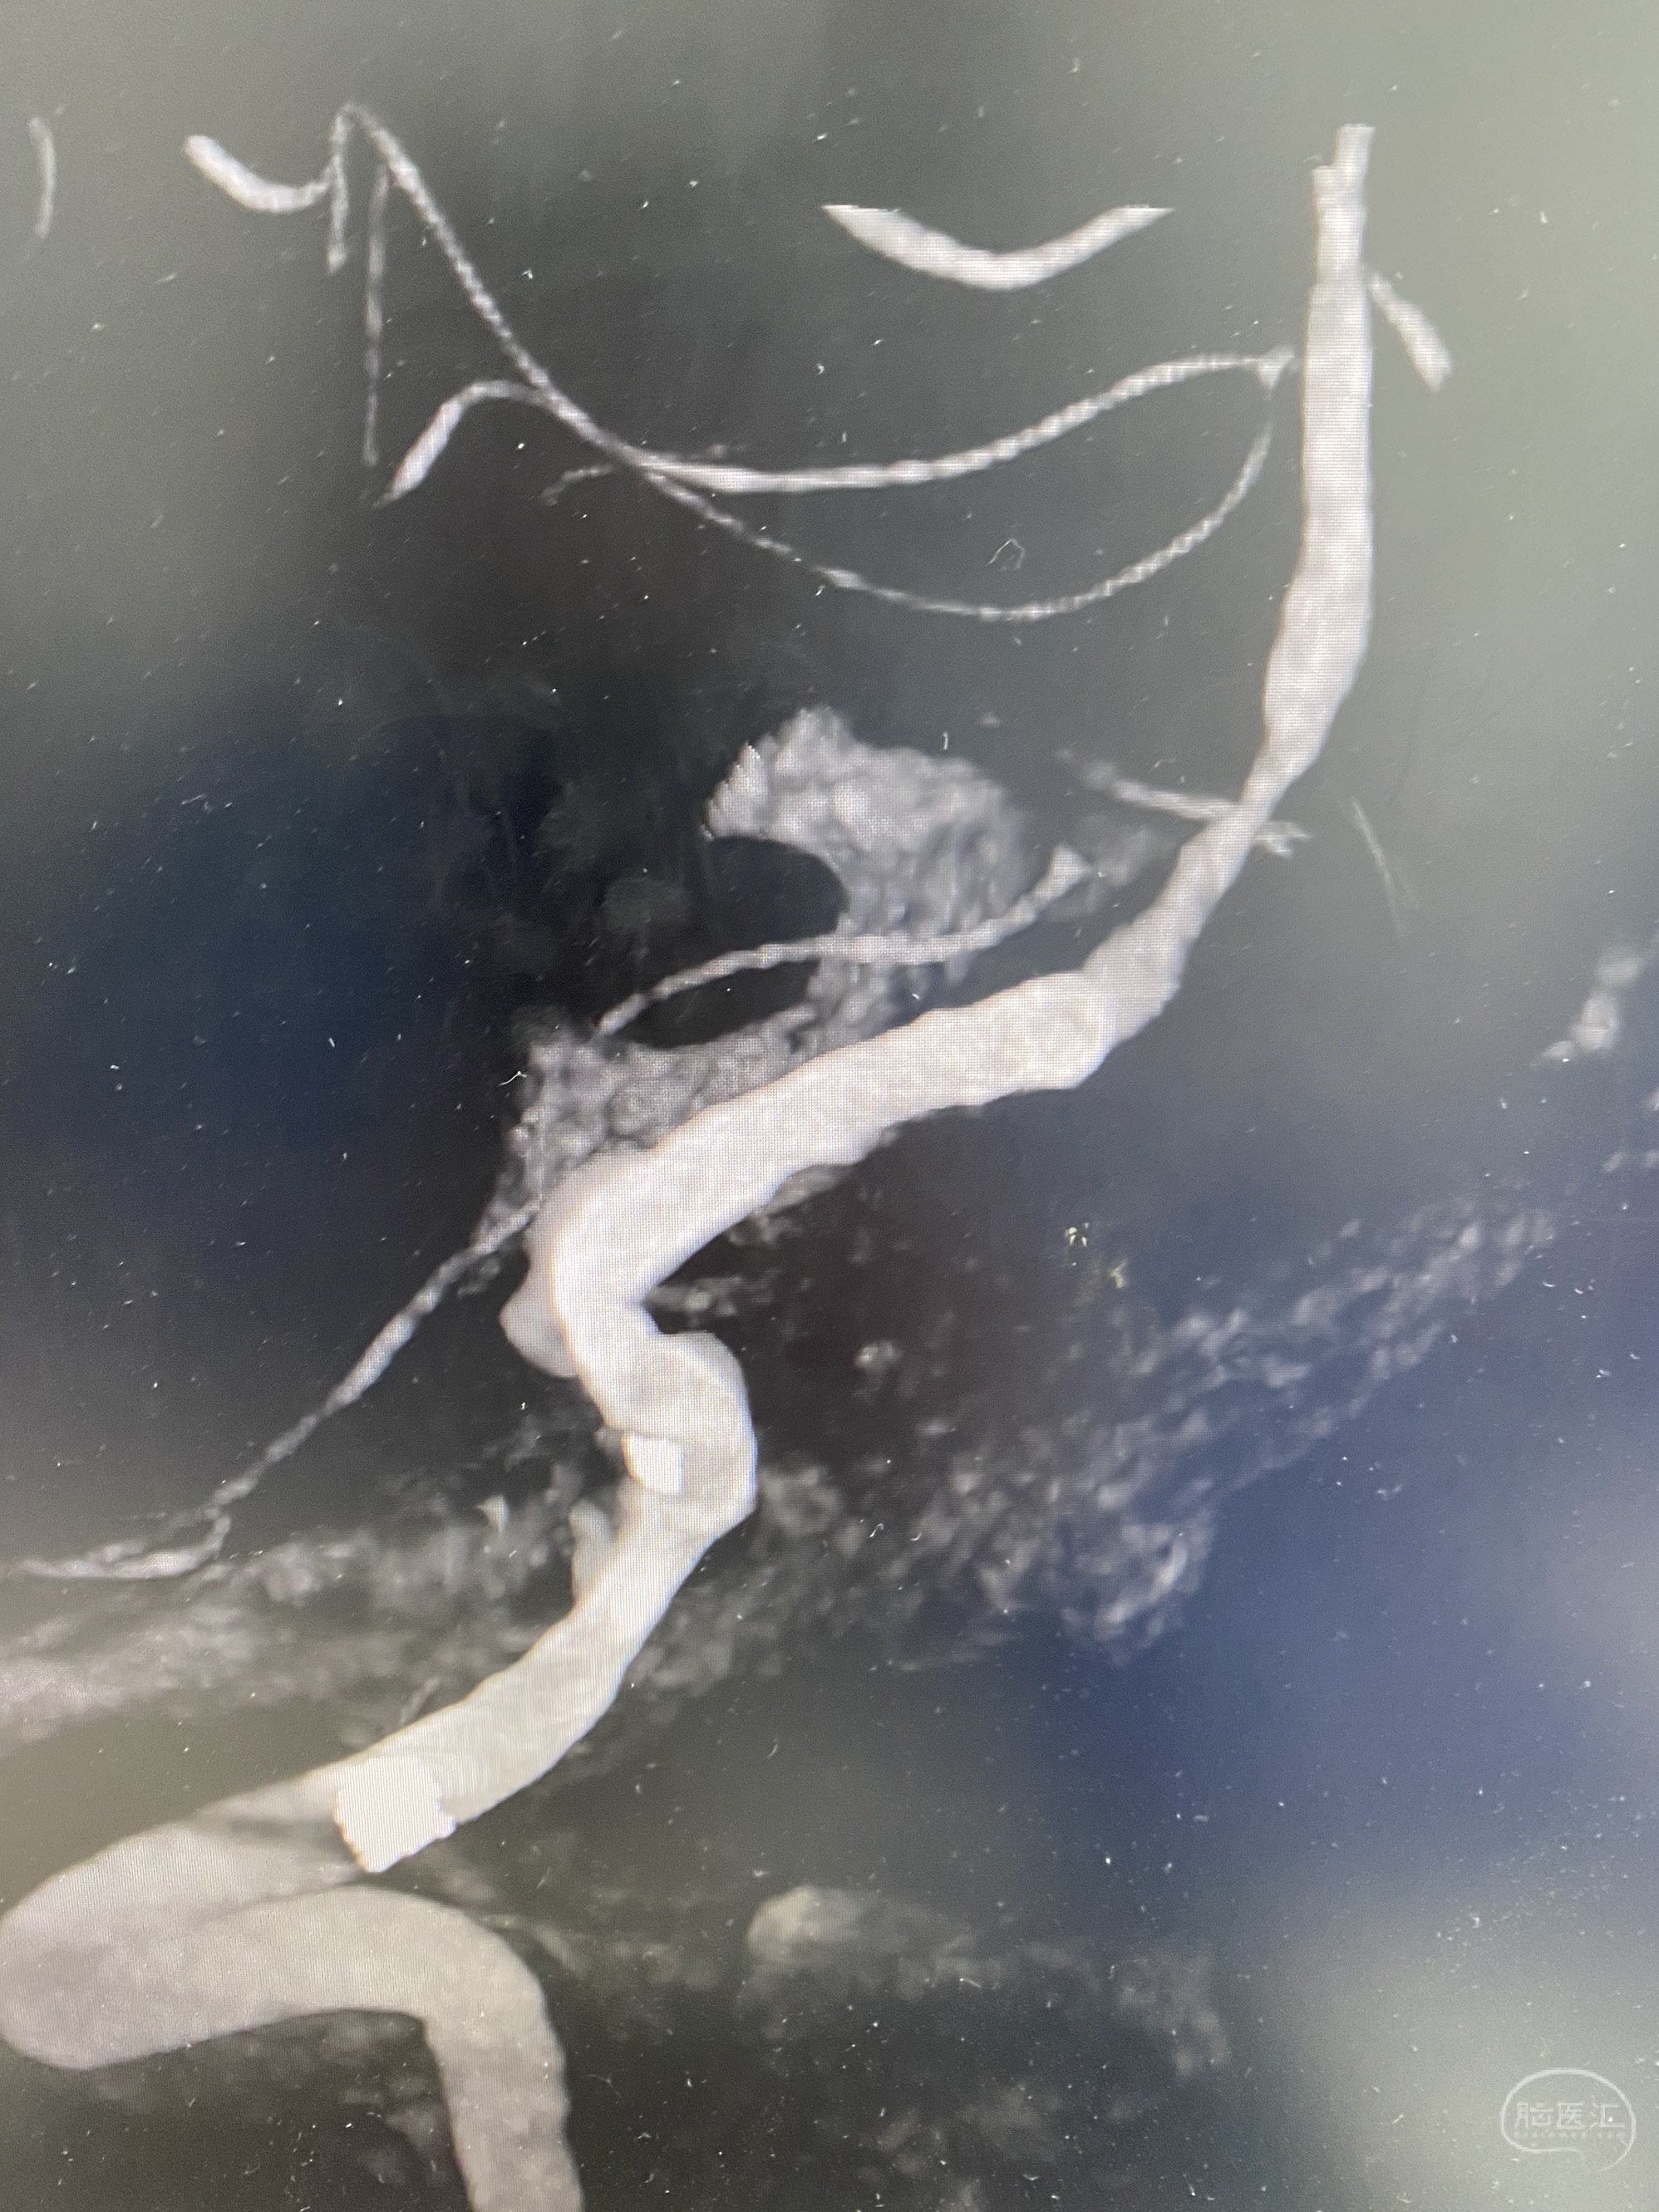

椎动脉颅内段多发夹层动脉瘤伴载瘤动脉狭窄pipeline flex植入

今日手术,TJG,M62Y,一期左侧颈动脉狭窄支架植入,二期椎动脉V4段多发夹层动脉瘤伴狭窄,常规支架辅助栓塞方法复杂又危险,血流导向装置植入快捷又安全。南阳市中心医院神经内科脑血管病介入团队pipeline flexFD植入两人导师资格。